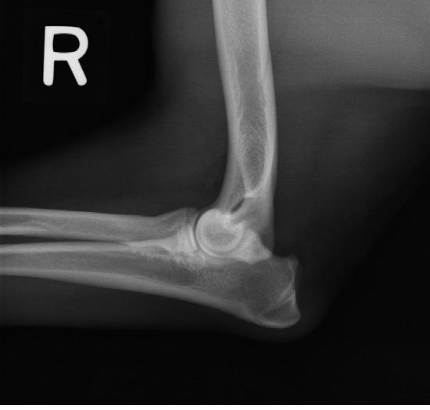

what radiographic view of the elbow is shown?

lateral view with elbow flexed 90 degrees

lateral view with elbow fully flexed

what structure of the elbow is focused on if we are doing a lateral view with the joint fully flexed?

olecranon process